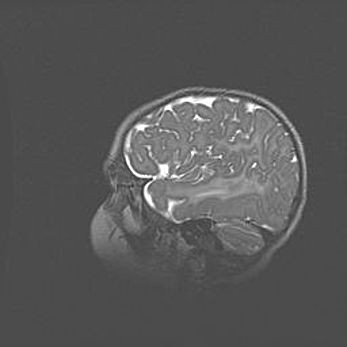

Открытая гидроцефалия.

Возраст: 9 месяцев 12 дней

Вес: 6800 г

Пол: мужской

Окружность головы: 41,5 см

Срок гестации: 28 недель

Гидроцефалия головного мозга у новорожденных имеет характерный признак: опережающий рост окружности головы приводит к визуально хорошо определяемой гидроцефальной форме сильно увеличенного в объёме черепа. Детские неврологи определяют следующие симптомы гидроцефалии у грудничков: выбухающий напряжённый родничок, частое запрокидывание головы, смещение глазных яблок к низу.